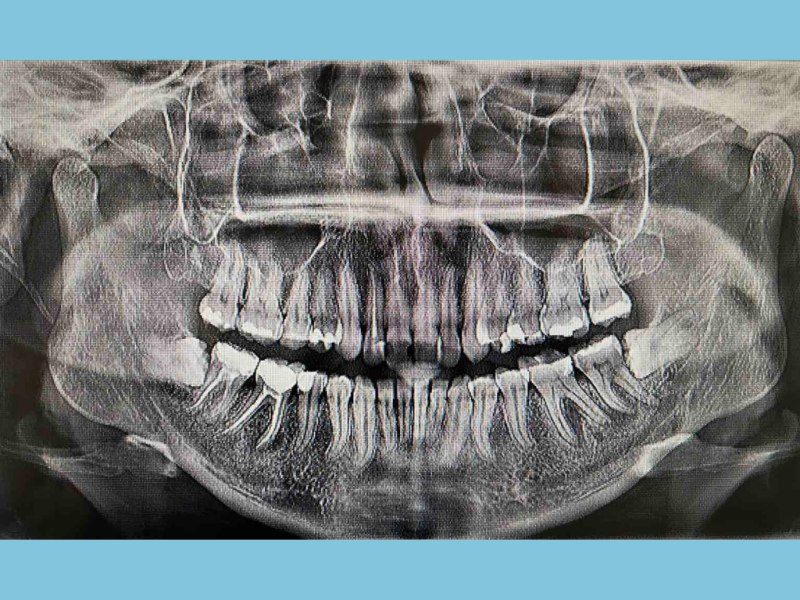

ORALNA HIRURGIJA

Ova stomatološka oblast podrazumeva ne samo vađenje zuba, već i saniranje lezija u području zubnog korena, kao i korigovanje širokog spektra defekata gingive i kostiju vilica.

U zavisnosti od stanja pacijenta i kompleksnosti problema, ove procedure sprovode se, najčešće, u lokalnoj anesteziji.

PARODONTALNA HIRURGIJA

Parodontopatija predstavlja ozbiljno i veoma progresivno oboljenje desni, koje može dovesti do gubitka zuba. Hirurškom i laserskom terapijom, u našoj ordinaciji se uspešno zbrinjavaju parodontalni džepovi, kao i uznapredovali proces parodontopatije. Na taj način, vrši se očuvanje dentalnog niza – njegove funkcionalnosti i estetike.

ZUBNI IMPLANTI

Ugrađivanjem titanijumskih zubnih implanata, omogućava se normalno funkcionisanje vilica. Implantologija svoju primenu nalazi u slučajevima gubitka zuba usled traume, karijesa ili parodontoze. Zubni implanti su biokompatibilni i uspešno srastaju sa zubnom kosti, zbog čega ih pacijenti doživljavaju kao prirodne zube.